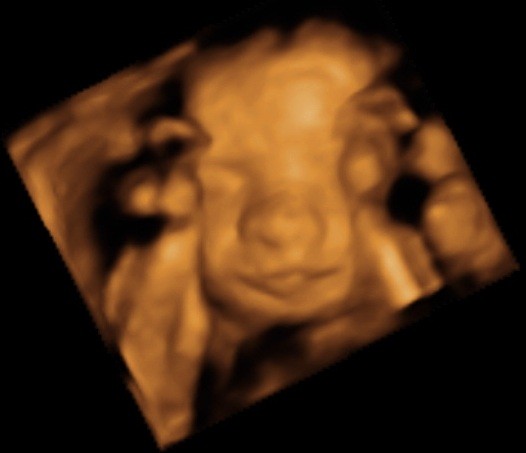

ślicznyNie wiem, ktory temat odpowiedni, wiec wstawie fotki naszego synka tutaj (nie sa to medyczne skany, wiec watek lekarski chyba nie pasuje, nie sa to tez zdjecia brzuszka...)

Zobacz załącznik 435457